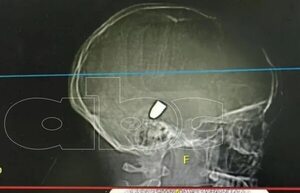

El dr. Elías Rolón nos comenta sobre el estado de salud de niña baleada en PJC . “El proyectil migró hacia el cerebelo y eso empeoró el edema. Se manejó la posibilidad de hacer una cirugía de descompresión. La tomografía de anoche mostró que no empeoró... [Leer más]

La pequeña que recibió una bala perdida en la cabeza tuvo un pequeño retroceso en su evolución, aunque permanece estable, aún con pronóstico reservado. Los médicos se plantean la posibilidad de una cirugía para descomprimir su cerebro, pero aguardan el... [Leer más]

Bala perdida tuvo una “migración” en la cabeza de la niña - Nacionales - ABC Color

La bala perdida que se encuentra en la cabeza de una niña de 13 años tuvo una “migración”, algo que llega a “ensombrecer” el pronóstico de la pequeña, dijo el Dr. Elías Rolón, director médico del Hospital Central del Instituto de Previsión Social (IPS). [Leer más]